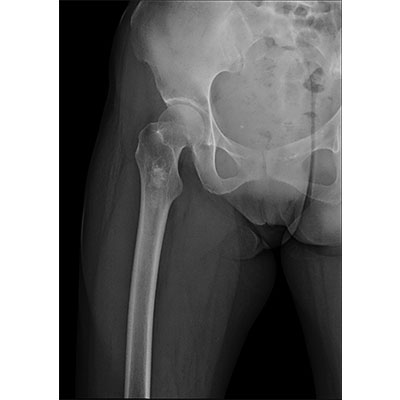

● 采用自主研發(fā)的技術(shù),在保證優(yōu)質(zhì)圖像的前提下,大大降低X射線劑量,用心呵護(hù)醫(yī)護(hù)工作者及患者的健康。

● 短曝光時間,便于老年人、兒童、殘疾人進(jìn)行臨床拍攝。避免這類群體因不能有效控制身體運(yùn)動等因素造成的運(yùn)動偽影,提高攝片質(zhì)量及效率。